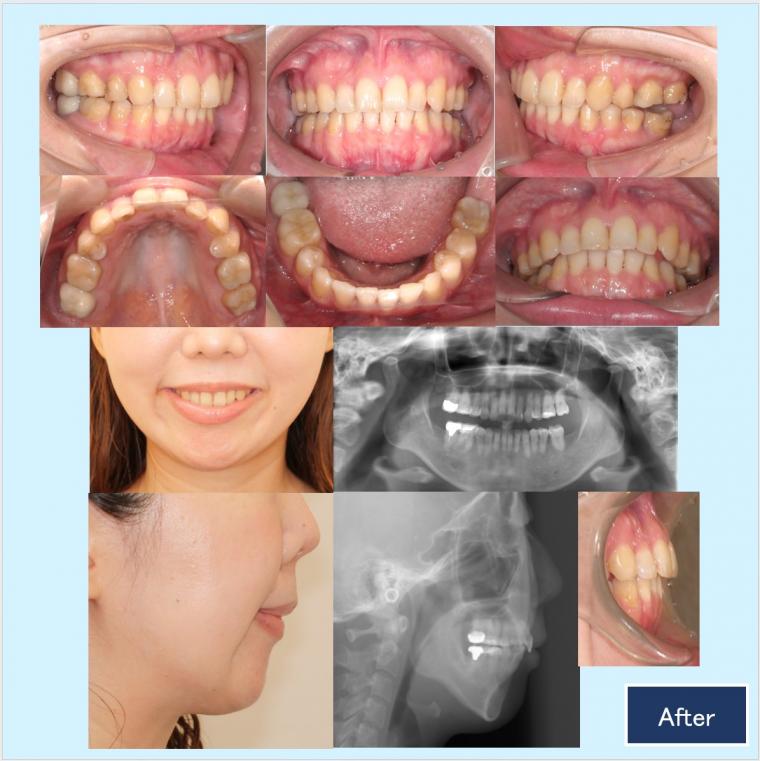

No.60 口ゴボと下顎後退症を口蓋型歯科矯正用アンカースクリュー(i-station)で改善した症例

『前歯で噛めない、あごがない、口ゴボで口が閉じれない状態を外科矯正は避けて治したい。』という主訴でした。上顎両側5番、下顎右側5番と予後不良である下顎左側6番を抜歯しました。

歯科矯正用アンカースクリュー植立を口蓋部(i-station)と歯槽部に併用して、抜歯スペースを利用して上下顎の叢生や上顎歯列全体の圧下による下顎のオートローテーションを致しました。咬合はもちろんですが、口元・側貌・スマイルラインとてもきれいになりました。

診断名:過大なオーバージェットと重度なHigh angleと叢生を伴う下顎後退症例

年齢:30代 治療期間:2年4ヵ月 治療回数:30回 初診時日時:2021年12月16日

抜歯部位:上顎両側5番、下顎右側5番と下顎左側6番